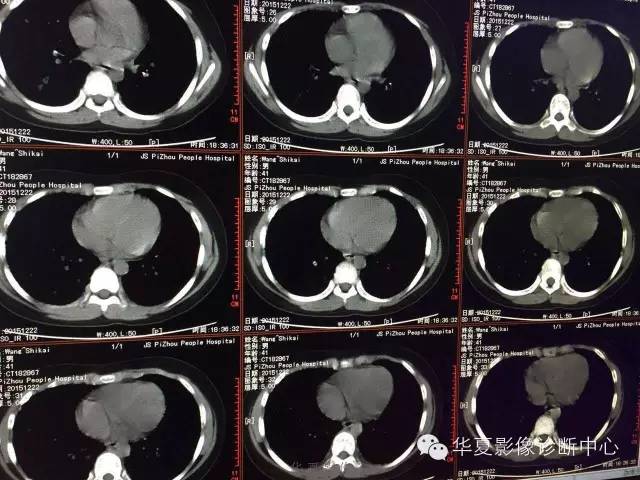

支原体肺炎1例CT影像表现

【病例】支原体肺炎1例CT影像表现